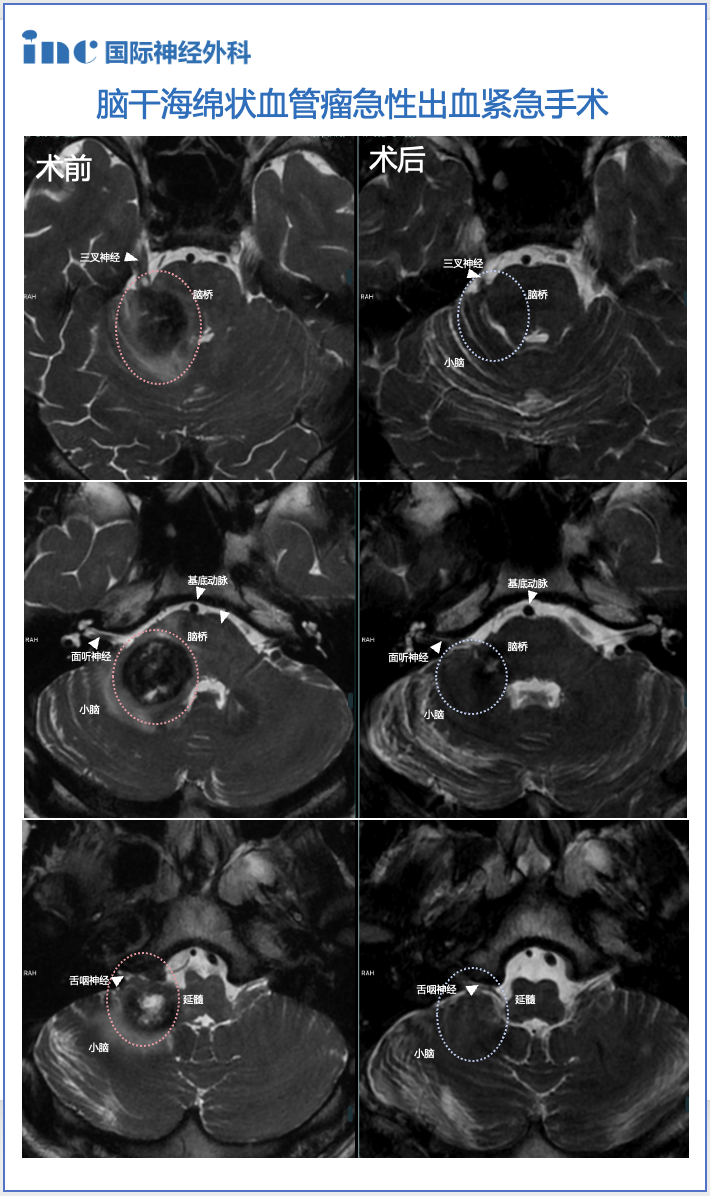

突发脑干出血事件 病危状态首次转运

初期,陈先生仅偶尔听闻儿子抱怨上学时经常出现头晕症状。彼时他被生活琐事缠身,未予充分重视,只是叮嘱儿子注意休息。未料荣荣此次头晕持续7天,并出现右侧耳鸣、右面部麻木及舌部麻木等系列症状。意识到情况异常后,陈先生立即带儿子前往医院检查,却被告知孩子脑干及右侧桥臂区存在异常信号,高度疑似海绵状血管瘤。此外,医生还在荣荣小脑内发现复杂静脉畸形,尤其海绵状血管瘤对侧区域。棘手之处在于静脉畸形中一条较大引流静脉大约在中线位置穿过脑桥。荣荣当前症状正是海绵状血管瘤导致出血所致,同时在脑干内病灶周围产生水肿。但由于病变位置特殊,医生最终建议陈先生可先继续观察孩子后续状况。

手术全切成功 儿子恢复超乎预期

术后当天ICU查房时,荣荣已经恢复意识,无新发神经损伤。巴教授检查了孩子的面部状况及吞咽功能,一切正常。术后第1天,巴教授再次告知陈先生:"术后MRI检查结果良好,无需担忧。"至术后第3天,荣荣状态进一步改善,术前头晕症状显著缓解,已可下床行走。陈先生见此情景无比欣慰——"他术前头晕极其严重,无法活动,非常难受,症状特别严重。但来到这边后,一切进展顺利。巴教授手术后第二天他就不再头晕,症状逐渐减轻,一天比一天好转。"

术后3个月,巴教授为荣荣进行随访检查,证实其右侧脑桥及小脑臂内较大海绵状血管瘤已完全切除!陈先生的心终于安定,家庭生活逐步回归正轨。